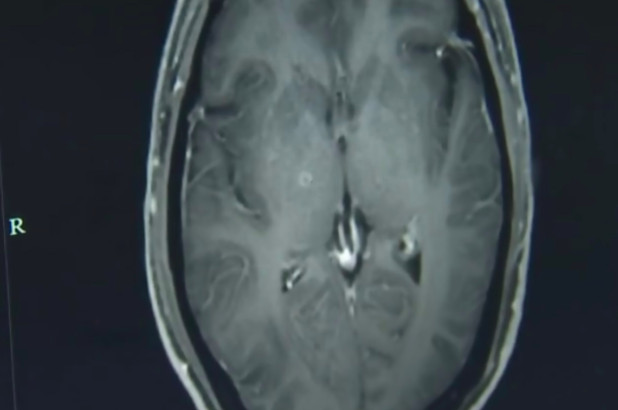

Ảnh chụp cắt não cho thấy não của người đàn ông bị nhiễm sán dây ký sinh, khiến ông này bị co giật và mất ý thức.

Jianrong giải thích, ấu trùng xâm nhập vào cơ thể Zhongfa thông qua hệ thống tiêu hóa và đi lên các bộ phận bên trên thông qua máu. Ông bị chẩn đoán mắc cysticercosis và neurocysticercosis và được cho dùng một loại thuốc chống ký sinh trùng và các loại thuốc khác để bảo vệ các cơ quan khỏi tổn thương thêm.